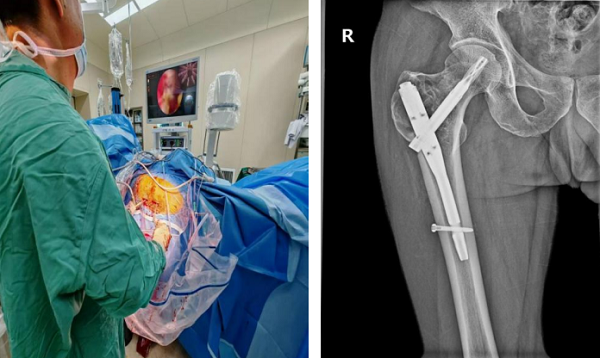

术后恢复效果超出预期:杜先生在术后第二天即可下床拄拐进行患肢不负重行走训练;术后1个月复查时,其髋部疼痛完全缓解,已能实现完全负重行走,影像学检查显示肿瘤病灶无扩大迹象,骨骼愈合情况良好。